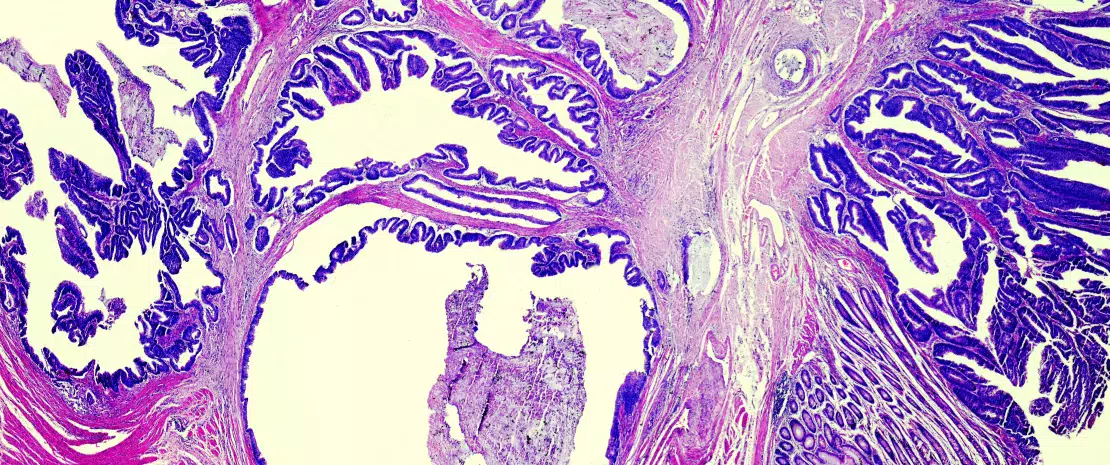

Pour le mettre en évidence, les chercheurs ont procédé en plusieurs étapes. D’abord, à partir de l’analyse des microbiotes de deux cohortes indépendantes de malades (total de 106 patients dont 34 ne répondaient pas au traitement), ils ont remarqué que l’abondance de la bactérie Bacteroides fragilis était significativement plus élevée chez les non-répondeurs, et que cette abondance était corrélée à un moins bon pronostic.

Les scientifiques se sont demandé si B. fragilis était en cause dans la chimiorésistance. Pour tester leur hypothèse, ils ont mis en culture des cellules cancéreuses humaines en présence de B. fragilis puis de deux médicaments de chimiothérapie, le 5-fluoro-uracile (5-FU) et l’oxaliplatine (OXA).

Les résultats indiquent que B. fragilis réduit bien la sensibilité des cellules cancéreuses à la chimiothérapie, notamment en supprimant l’apoptose induite par ce traitement. La même expérience in vivo sur des modèles murins de CCR confirme ces résultats avec, après traitement par 5-FU et OXA, la présence d’un plus grand nombre de tumeurs chez les souris exposées à B. fragilis que chez celles qui n’y étaient pas exposées.

Les chercheurs se sont alors demandé par quelles interactions bactérie-cellule cancéreuse la voie Notch1 était activée. Une observation au microscope électronique à balayage de cellules in vitro et in vivo leur a permis de constater que B. fragilis adhérait bien aux cellules cancéreuses.